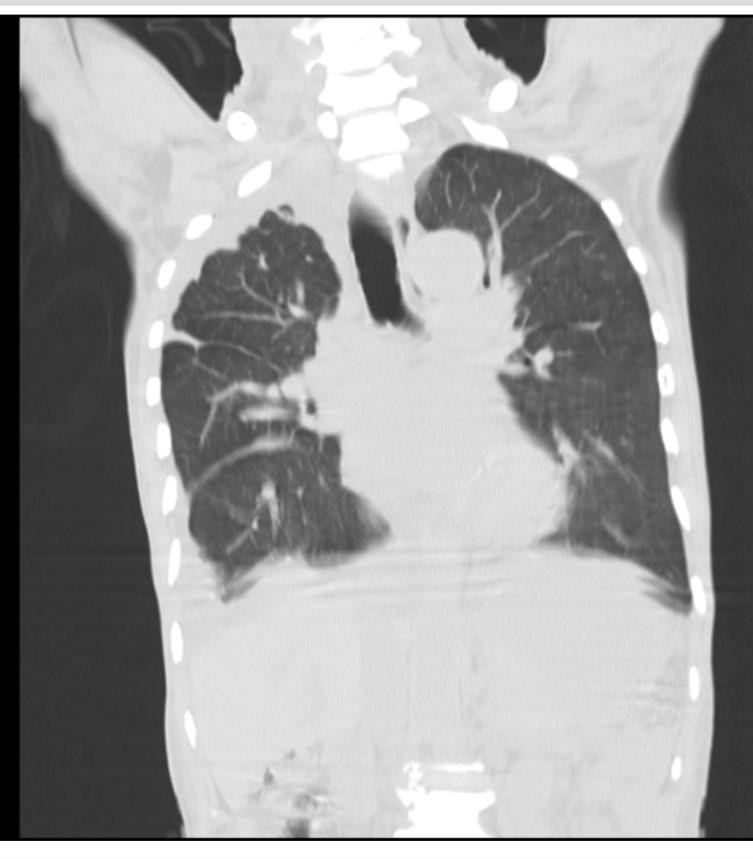

65 YEAR OLD MALE PATIENT WITH FEVER ,COUGH, SHORTNESS OF BREATH

65 year old man presented with the complaints of

He was apparently alright one year back after which he started to notice reduced urine output. He would often feel dyspneic after walking for a short duration since several months. Since 1 month he has been experiencing low grade fever on and off along with cough without expectoration. He also says he has been even more dyspneic over the last one month. He says he has been feeling numbness in both his lower limbs.Bilateral swelling of both his lower limbs also developed gradually extending to his knees. He also tells that there has been slippage of footwear since 1 week. He finally visited a local hospital, where in he was diagnosed with CKD with Heart failure and he received Spironolactone 50mg plus torsemide 20mg. He was even diagnosed to be a hypertensive and diabetic.

On inspection - Barrel shaped chest was present

Respiratory examination -

Dullness + in Bilateral IAA, ISA

Vocal resonance reduced in right ICA,IMA,IAA,ISA

Inspiratory crepts + Bilateral IMA,IAA,ISA

decreased breath sounds+ in ISA

Juxtphrenic sign - small triangular opacity near done of diaphragm due to stretching of inferior accessory fissure or inferior pulmonary ligament